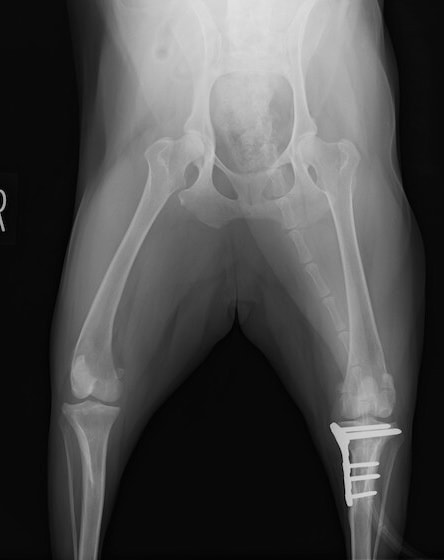

雑種 5歳

左後肢の挙上を主訴に来院されました。触診にて両関節の前方引き出し兆候、両膝蓋骨の内方脱臼を認めました。関節液検査より免疫介在性多発性関節炎は否定的でした。レントゲン検査にてfat pad signを伴う関節炎が認められたことから、前十字靭帯断裂と膝蓋骨内方脱臼(左GradeⅢ 右GradeⅢ〜IV)併発と診断し、手術を行いました。

手術は片足ずつ行い、両膝とも術中の関節鏡検査にて前十字靭帯の完全断裂と半月板損傷を確認しました。TPLO、半月板切除と滑車溝形成を始めとした膝蓋骨脱臼整復術を実施いたしました。膝蓋骨の安定化を測るために外側支帯を強固に縫合し、内側支帯は切除し縫合せずに開放状態にしています。

術後の歩行状態は良好です。

術前正面像

術後左後肢正面像

術前のTPAは左後肢33.1°右後肢26.8°でしたがTPLO実施により左後肢5.5°右後肢12°に矯正されました。